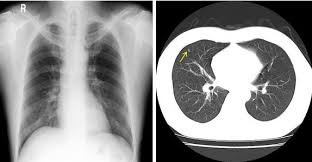

폐결절(pulmonary nodule)은 폐 안에 지름 3cm 이하의 작은 덩어리나 불투명 부위로, 흉부 X‑선이나 CT 검사에서 우연히 발견되는 경우가 많습니다. 대부분은 무증상이며, 양성인 경우가 많지만 일부는 악성(암)일 수 있어 주기적인 관찰이 필요합니다.

- 흉부 X‑선 또는 흉부 CT로 발견

- 결절 크기·형태·경계·석회화 여부 등 특징 분석